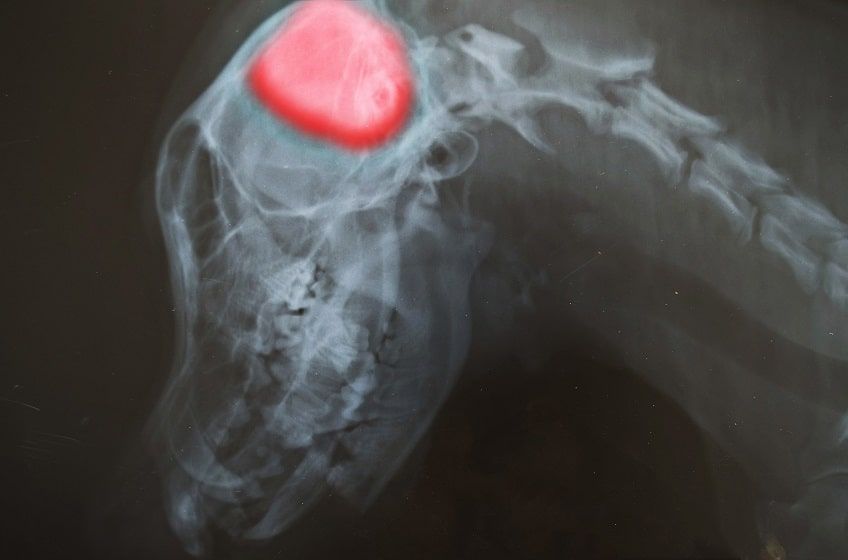

Rozpoznanie udaru u psa nie jest łatwym zadaniem. Dokładny wywiad lekarski i badania krwi pozwolą wyeliminować prawdopodobieństwo innych chorób mogących dawać podobne objawy. Następnie pies z podejrzeniem udaru musi być poddany dokładnemu badaniu neurologicznemu, które pozwoli ustalić, jaki obszar mózgu doznał urazu.

Nieraz konieczne jest przeprowadzenie dodatkowych, specjalistycznych badań, takich jak tomografia komputerowa i rezonans magnetyczny. Takie analizy pozwolą dokładnie określić charakter udaru i jego lokalizację w mózgu. Niestety, większość przychodni weterynaryjnych nie dysponuje potrzebnym do tych badań sprzętem, konieczne więc może być udanie się ze zwierzakiem do specjalistycznej kliniki neurologicznej.